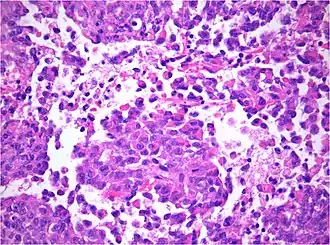

Namensgebend und für die feingeweblichen (histologischen) Eigenschaften typisch sind relativ große Tumorzellen, die randständige, hervorstechende Kernkörperchen (Nukleolen) und Einschlüsse in ihrem Zellkörper besitzen, sogenannte rhabdoide Tumorzellen. Sie erinnern in ihrem Zellbild an einen bösartigen Weichteiltumor, das Rhabdomyosarkom. Mitotische Aktivität, Zelldichte und Kernpolymorphie sind erhöht. Tumornekrosen sind häufig. Der Tumor wächst unstrukturiert oder in papillären Strukturen, was die Abgrenzung gegenüber Plexuskarzinomen schwierig machen kann. Andererseits kommen neben Abschnitten mit rhaboiden Tumorzellen häufig auch kleinzellige Anteile vor, deren Histologie dem anderer embryonaler Tumoren wie dem Medulloblastom ähneln.